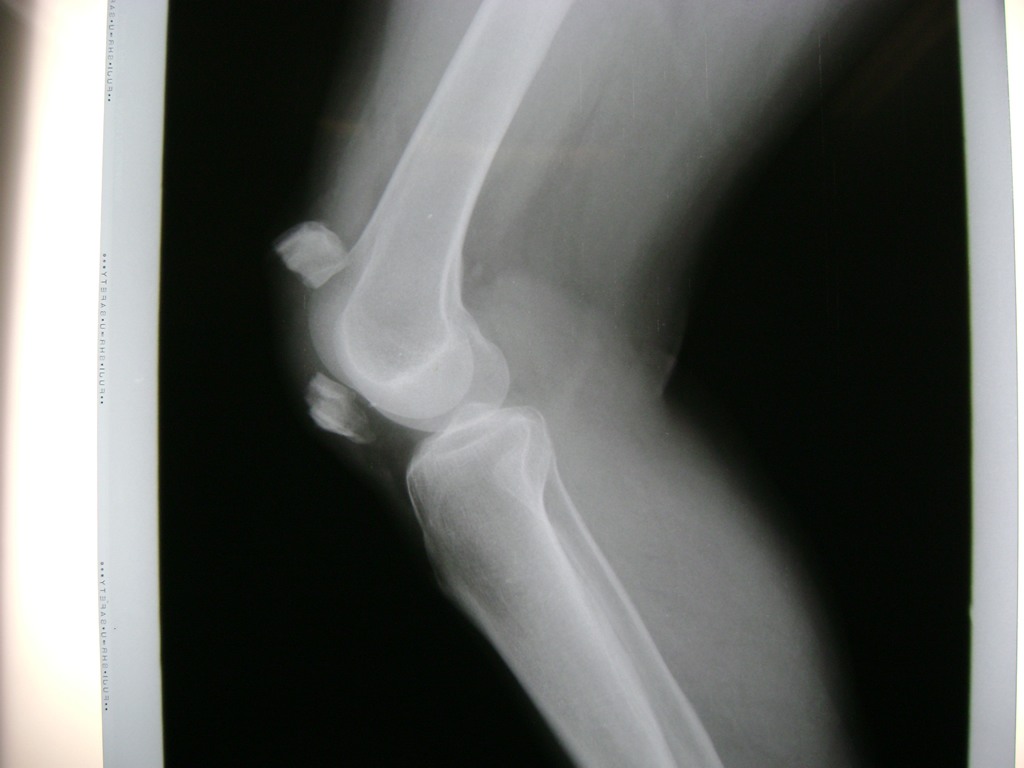

Cirugías de Húmero - Rodilla

La artroscopia de rodilla es un cirugía en el cual la estructura interna de la articulación es examinada ya sea para realizar un diagnostico o para realizar un tratamiento, este procedimiento se realiza utilizando un instrumento parecido a un pequeño tubo llamado artroscopio.